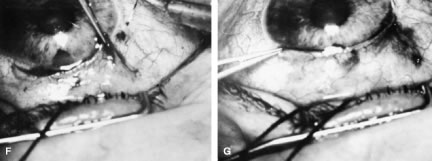

To obtain increasingly lower IOP, it is necessary to modify surgical technique (Table 15). By performing guarded filtration procedures so that the sutures can be released postoperatively, with the use of either laserable or releasable sutures, a lower final IOP can be obtained in some cases. This technique allows a bleb to develop that is similar to that seen in a full-thickness filtration procedure. Such blebs tend to be thin, polycystic, and located directly at the limbus, in contrast to those seen after classic trabeculectomy, which are thicker, lower, more diffuse, and more posterior. When antifibrosis agents (antimetabolites and corticosteroids) are added to procedures designed to develop full-thickness filtration, IOP tends to be sharply reduced.27–29 The blebs associated with the use of 5-fluorouracil (5-FU) and mitomycin are an exaggeration of the full-thickness type of bleb: Often, they are extensive, sometimes involving 360 degrees of the anterior surface of the globe, and the conjunctiva tends to be thin and completely ischemic.30–34

The thin filtration blebs associated with the use of mitomycin or 5-FU may rupture spontaneously. They tend to be so high that the adjacent cornea becomes dry, with the development of an uncomfortable delle. Ptosis tends to develop, and patients often are photophobia One of the most serious concerns is the high incidence of endophthalmitis in patients with thin blebs. When full-thickness blebs were the routine type of glaucoma procedure, endophthalmitis would develop in approximately 1% of patients. When 5-FU was used to develop filtration blebs inferiorly, an 8% rate of endophthalmitis was reported.35–42 Hypotony, even in the absence of a thin bleb, introduces serious problems. The soft eye does not maintain a constant optical state, and it has a constantly changing amount of astigmatism that makes it impossible to correct. Each time the patient blinks, the amount of astigmatism changes. Macular and disc edema cause reduced central acuity and deterioration of the visual field, and the globe may have a constant, visceral ache. Patients with such eyes are not comfortable.